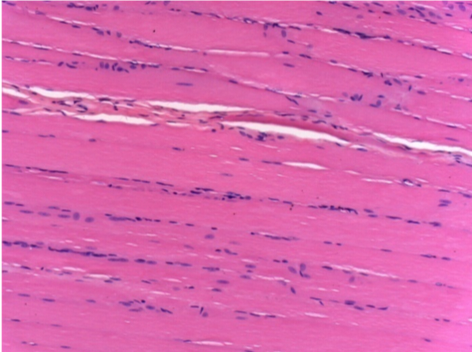

Через 10 днів після ін'єкції Ендопіл 0,1 мл в правий претибіальний м'яз.

Тут можна побачити утворення вакуолей, які оточені лімфоцитами. Вакуолі відрізняються від некрозу тканини. Присутність лімфоцитів пов'язана з проникністю клітинних мембран.